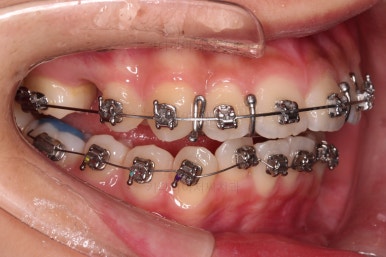

위아래 치열이 매우 고르게 되었으며, 이제부터는 발치공간을 줄여나가면서 교합을 맞춰 나가면 됩니다.

이번 환자분 같이 편악발치의 경우에는 윗니에만 발치 공간이 있고, 치아 사이즈의 부조화가 생겨서 발치 공간이 남거나 다 모아놔도 추후 재발이 되는 경우가 많습니다.

굉장히 디테일한 치료계획과 수행이 중요합니다.

이번 환자분도 다양한 테크닉으로 편악발치이지만 공간이 잘 줄어들 수 있게끔 치료해 나갑니다.

입매, 웃을 때의 입술선과 치열의 조화 등을 체크해줍니다.

디테일한 마무리를 하고 종료합니다.